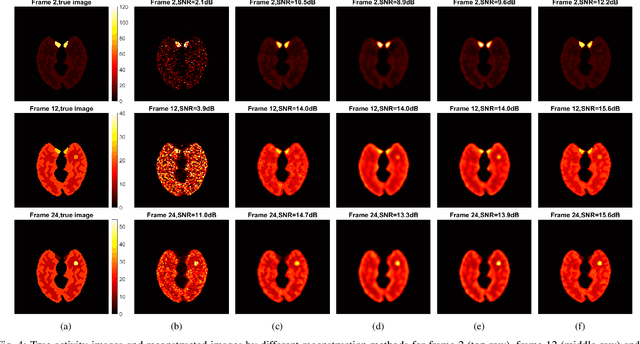

Image reconstruction of low-count positron emission tomography (PET) data is challenging. Kernel methods address the challenge by incorporating image prior information in the forward model of iterative PET image reconstruction. The kernelized expectation-maximization (KEM) algorithm has been developed and demonstrated to be effective and easy to implement. A common approach for a further improvement of the kernel method would be adding an explicit regularization, which however leads to a complex optimization problem. In this paper, we propose an implicit regularization for the kernel method by using a deep coefficient prior, which represents the kernel coefficient image in the PET forward model using a convolutional neural-network. To solve the maximum-likelihood neural network-based reconstruction problem, we apply the principle of optimization transfer to derive a neural KEM algorithm. Each iteration of the algorithm consists of two separate steps: a KEM step for image update from the projection data and a deep-learning step in the image domain for updating the kernel coefficient image using the neural network. This optimization algorithm is guaranteed to monotonically increase the data likelihood. The results from computer simulations and real patient data have demonstrated that the neural KEM can outperform existing KEM and deep image prior methods.